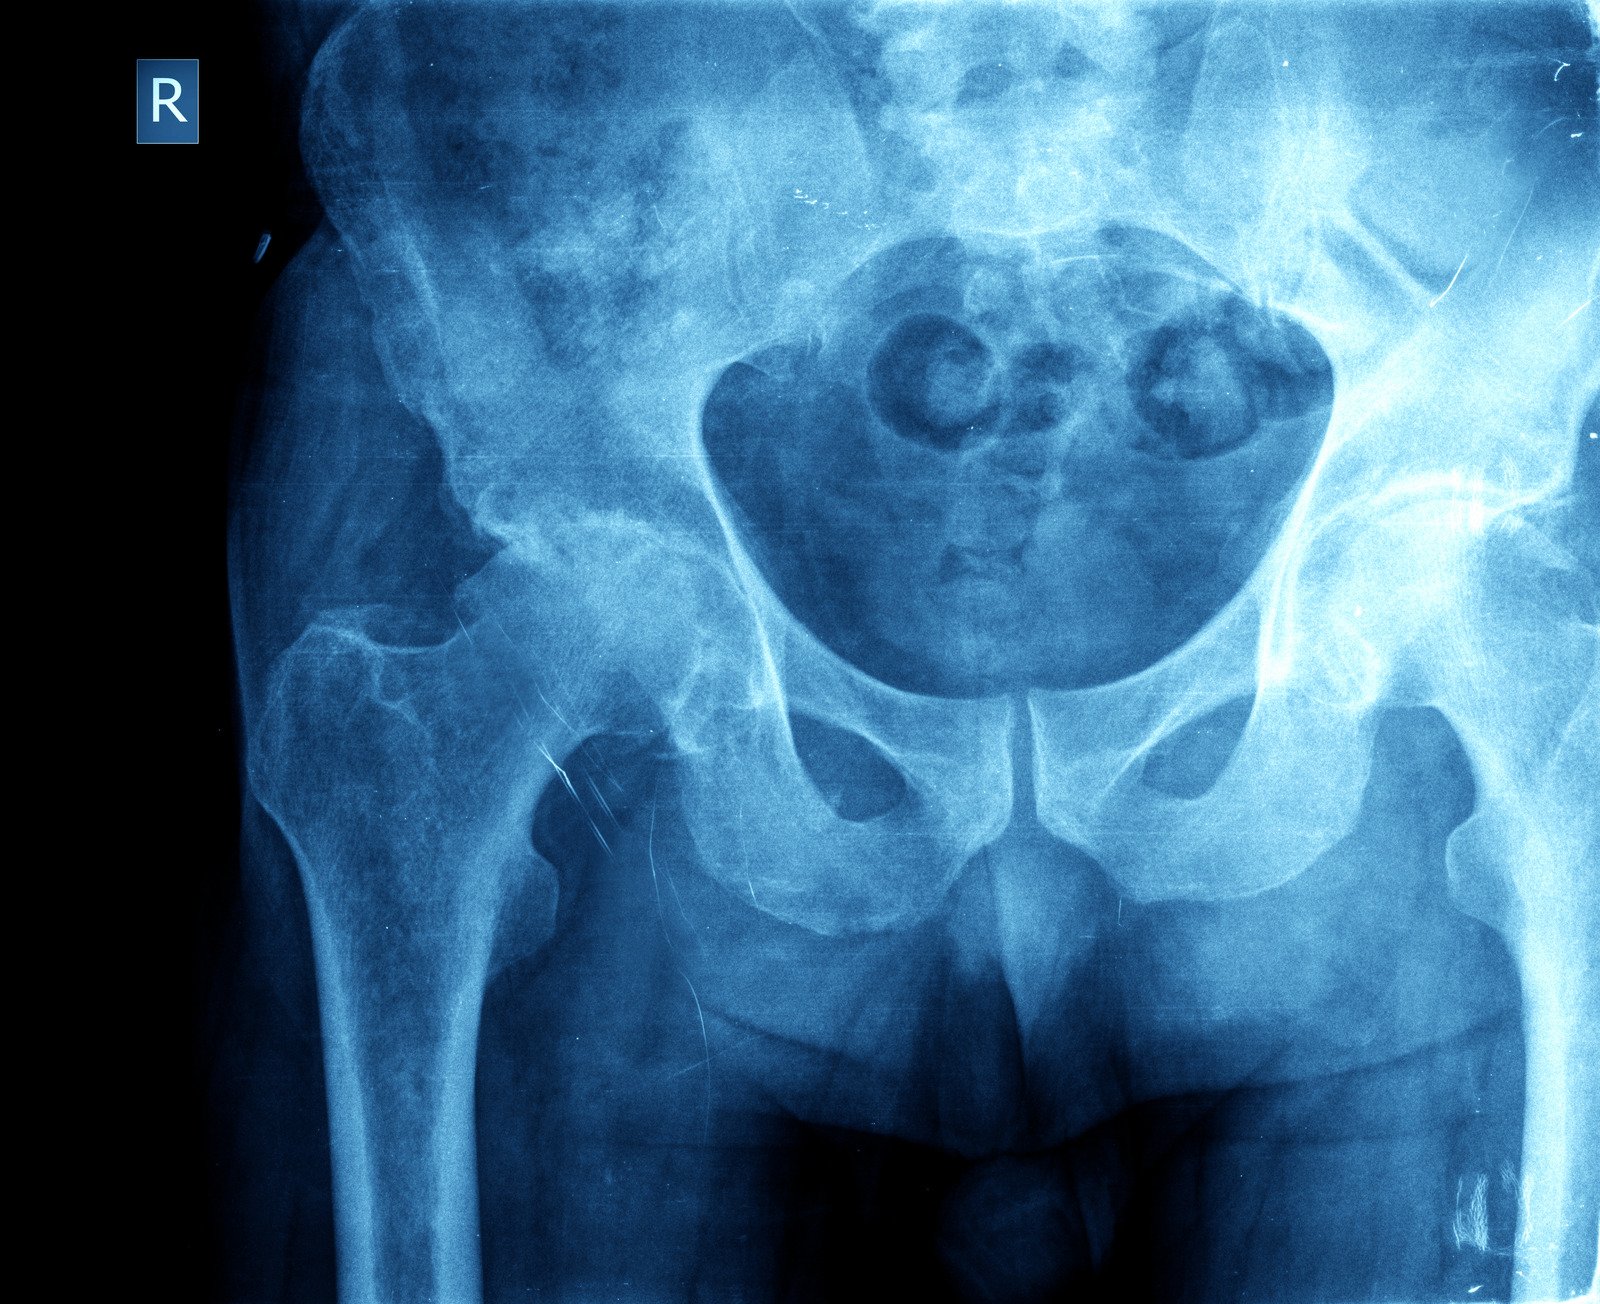

고관절 골절은 대퇴골(넓적다리뼈)과 골반을 연결하는 부위에서 뼈가 부러지는 부상을 의미합니다. 주로 대퇴골 경부와 대퇴골 전자부에서 발생합니다.

고관절 골절의 주요 증상은 다음과 같습니다:

심한 통증: 특히 고관절 부위에서 심한 통증이 느껴집니다.

움직임 제한: 다리를 움직일 수 없거나 움직이기 어려워집니다.

다리 변형: 부러진 다리가 짧아지거나 이상한 각도로 변형될 수 있습니다.

부종 및 멍: 부상 부위에 부종과 멍이 생길 수 있습니다.